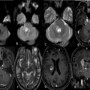

Axial DWI, FLAIR and T2W imaging (A,B,C) shows focal ovoid diffusion restriction in right dorsal pons with linear extension of hyperintense signals across lateral surface of pons and middle cerebellar peduncle.

(D) Axial T1W post contrast sequence shows ovoid enhancement of right dorsal pons with linear streak of enhancement along right lateral surface of pons and MCP. Enhancement of trigeminal nerve along the cisternal segment and in Meckel’s cave.

(E) Axial T1W post contrast sequence shows enhancement of right petrous apex.

(F) Axial T2W and (G)(H) T1W post contrast images shows ring enhancing lesions in right corona radiata and adjacent basal ganglia with surrounding oedema extending along the corticospinal tracts of the corona radiata, internal capsule, midbrain and cerebral peduncle.